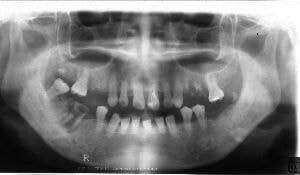

治療例2 (補綴処置+矯正)